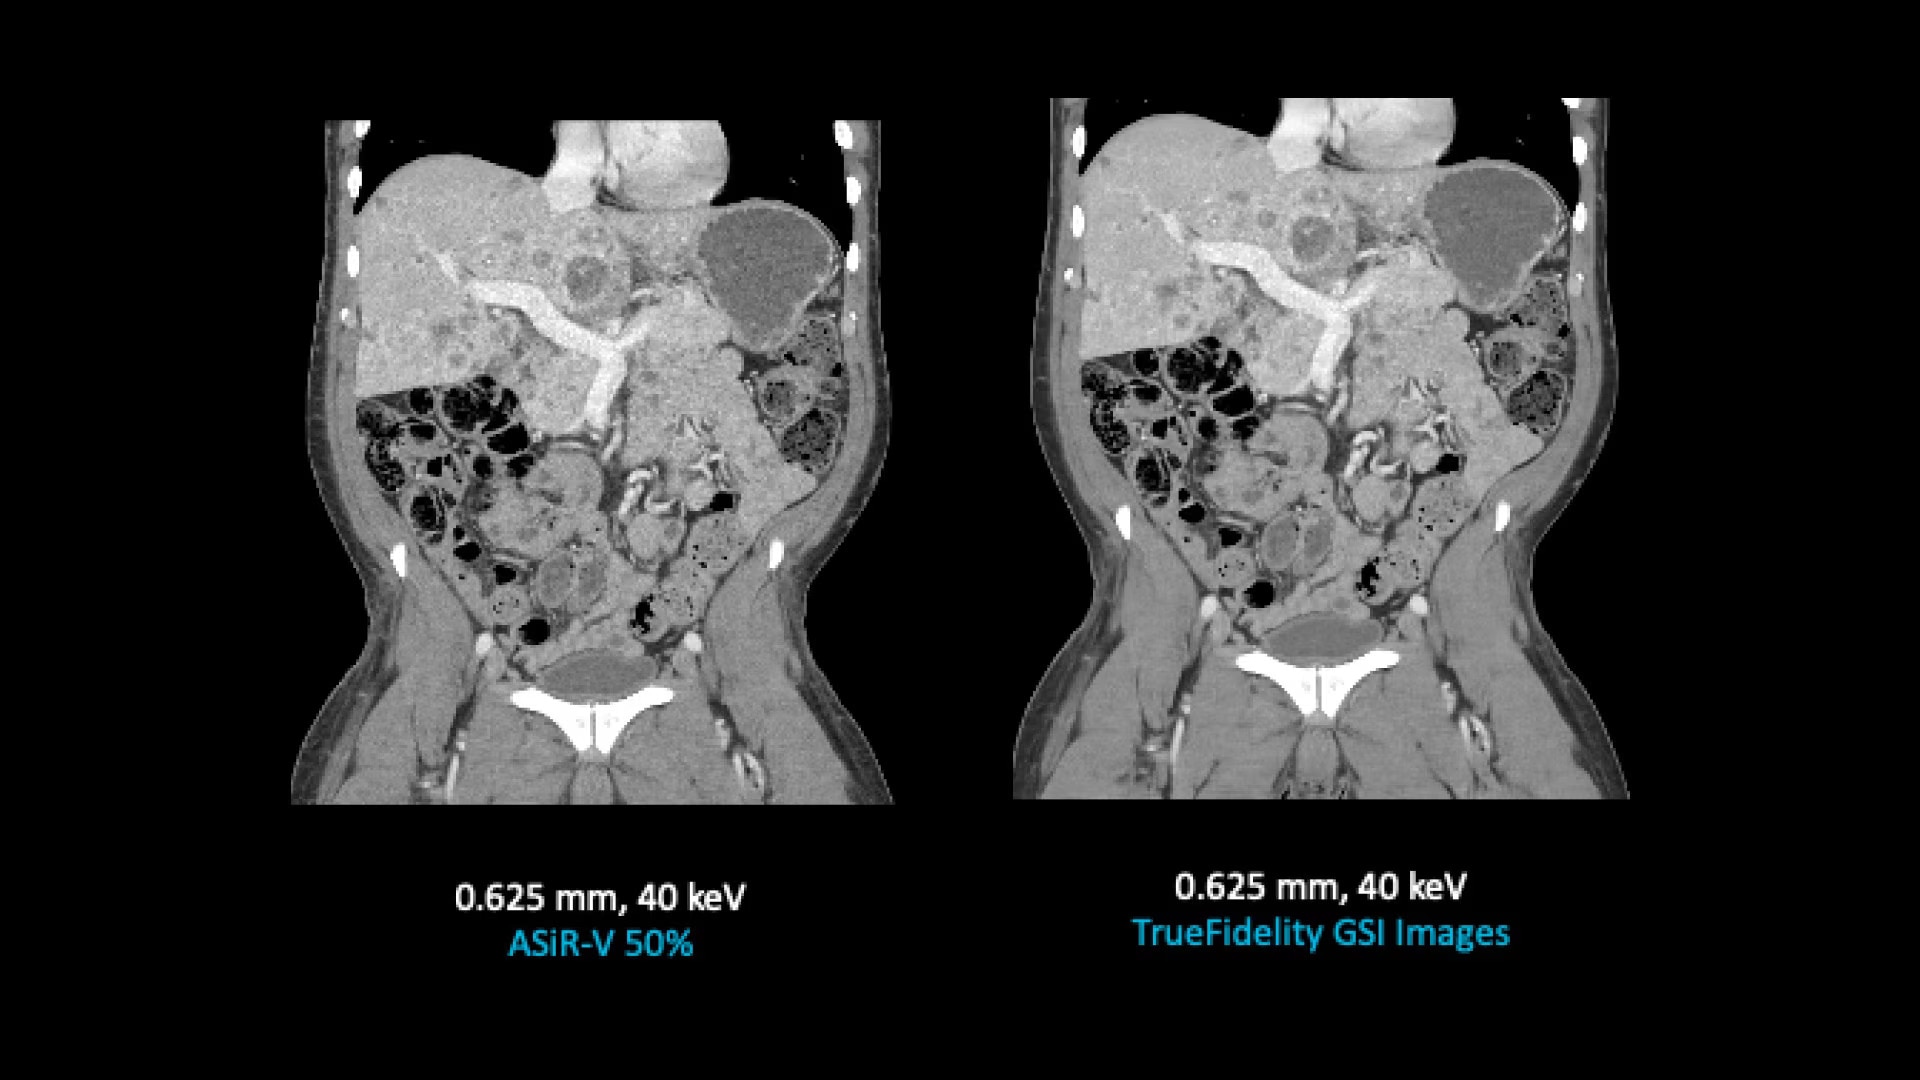

TrueFidelity for GSI now brings the potential to substantially reduce the image noise in all spectral image types

From virtual monochromatic images to material image pairs and virtual non-contrast images, with and without metal artifact reduction. Specifically, reducing the image noise inherent with low keV images resolves one of the traditional technical challenges in adopting more dual-energy protocols across the full patient population.